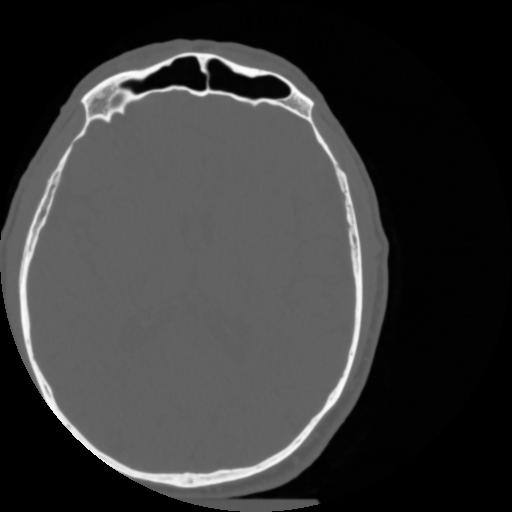

4 CEREBRO,,Vol,0.5,CEREBRO,,